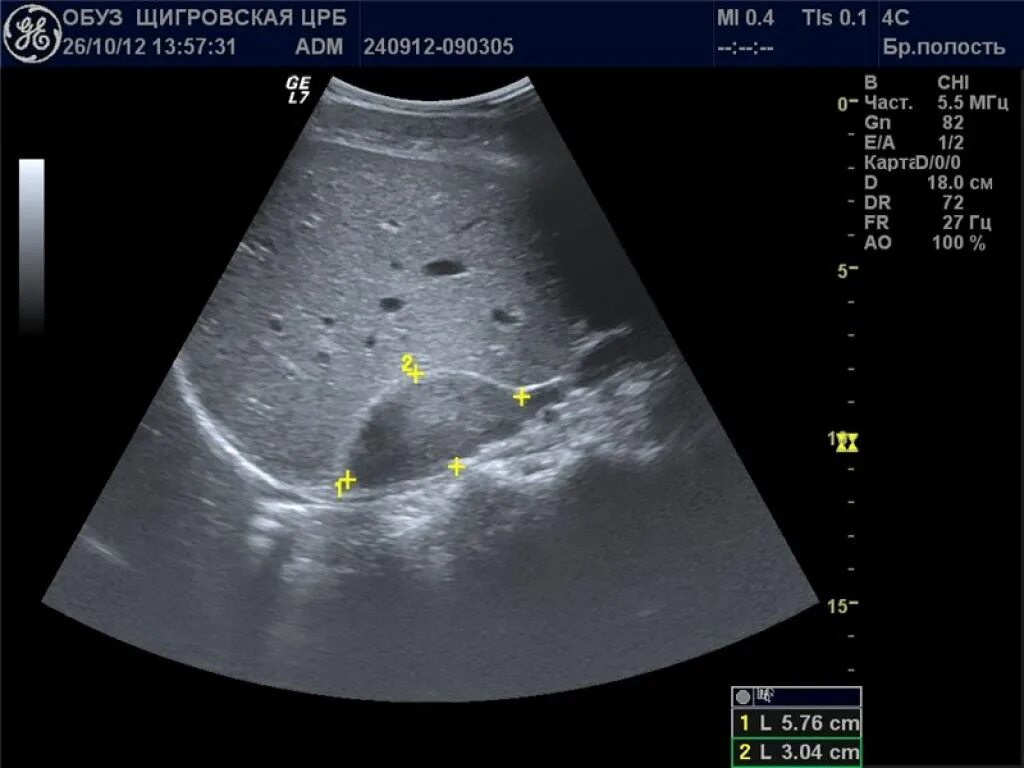

Узи надпочечников и забрюшинного пространства подготовка